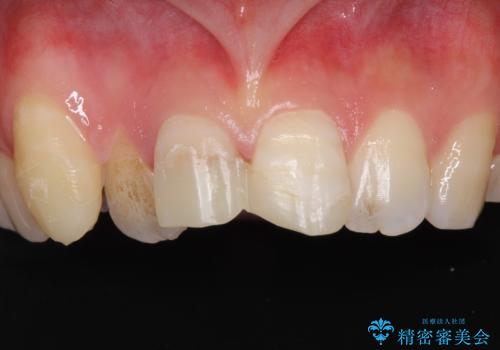

[ 矯正と補綴、総合歯科治療 ] クロスバイトを避ける前歯部審美ブリッジ

![[ 矯正と補綴、総合歯科治療 ] クロスバイトを避ける前歯部審美ブリッジの症例 治療前](https://seimitsushinbi.jp/wp/wp-content/uploads/2021/07/IMG_9914-500x350.jpg?v=1626697179)